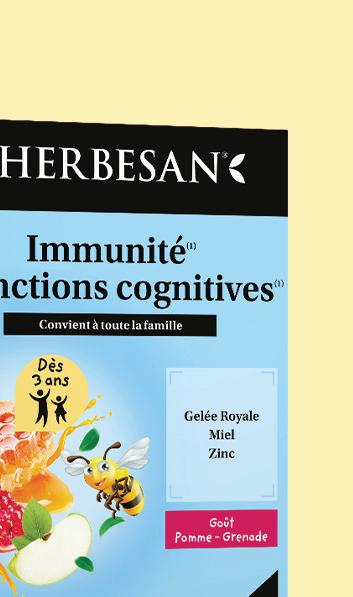

HERBESAN